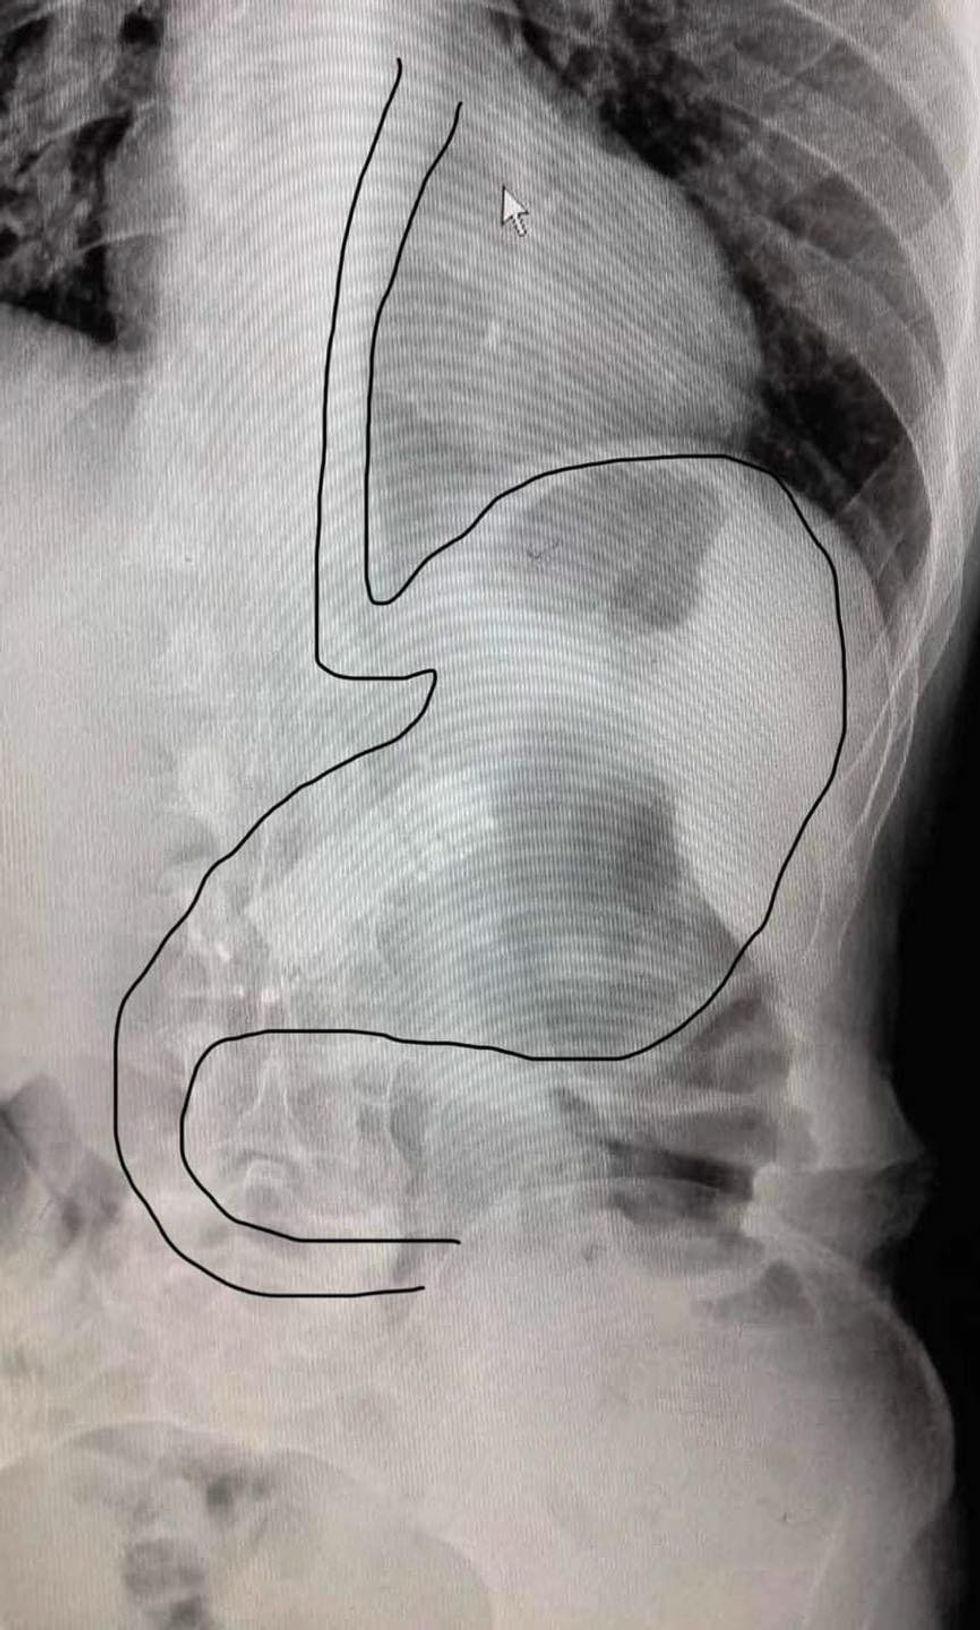

“Largimi i trupit të huaj nga stomaku ( telefon) Pacienti NN, me çrregullime depresive, duke u trajtuar për semundje të varshmërisë, sillet nga familjarët në ordinancën OSG në Malishevë. Me ç’rast dhe i largohet trupi i huaj nga lukthi, me endoskop fleksibil duke manovruar me aksesorët përkates, me asistim të dr. Taulant Kryeziut dhe infermieres Florida Shala".

"Procedura kryhet me sukses pa komplikime! Pacienti referohet për trajtim të mëtejmë tek psikiatri”, njofton ordinanca./Telegrafi/